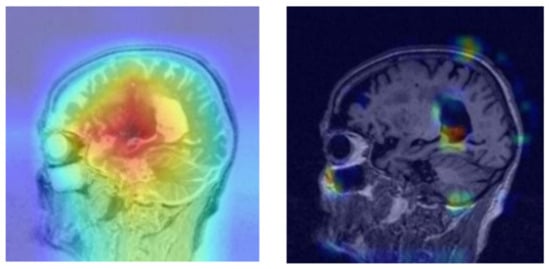

The challenges associated with diagnosing and predicting the progression of Alzheimer’s disease (AD) have been mitigated by using artificial intelligence (AI), particularly in image data analysis. However, in contrast to various brain disorders, AD remains difficult to comprehend despite being relatively easier to categorize based on established features. This study utilized the glass-box methodology to illustrate that the deep learning model generated positive predictions corresponding to the specified characteristics. What makes this research unique is the employment of the channel-wise attention mechanism not only to the deep learning model but also the XAI model, as shown in Figure 9, wherein the left shows the base Grad-CAM with a generalized heat map while the right shows the model with channel-wise attention applied, returning a well-defined heat map. The image on the left of Figure 9 was created using traditional Grad-CAM and, in comparison to our approach that hinges on an attention mechanism, it is evident that the heat map generated with channel-wise attention highlights the region of interest more accurately, which is in line with the medical literature on MCI diagnosis. The hippocampal area shows early signs of degradation for cases of mild cognitive impairment. While conducting this study, a few challenges were met during the conceptualization process. It was not straightforward when deciding which techniques to experiment with in order to avoid redundant output while supplementing the study collectively. Since the quickshift method is highly sensitive, it called for gradual hyperparameter tuning to obtain an acceptable kernel size of 70. The application of this mechanism improves the quality of the explanation on a more granular scale in contrast to traditional tuning, since each channel in the feature map is considered separately, wherein the focus is only on the most relevant channels. This approach verifies the classification while enhancing localization and the overall scope of this methodology is not limited to MRI studies; our method can be employed for generalized imaging tasks such as object detection. The flexibility of this framework also allows for experimentation with multimodal data such as MRI and diffusion tensor imaging (DTI).

Figure 9. Comparison between Grad-CAM without channel-wise attention (Left), which highlights a generalized region, and Grad-CAM with the attention mechanism (Right), which is more localized close to the hippocampal region.